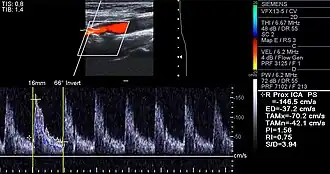

Besides the traditional diagnostic methods such as angiography and stress-testing, other detection techniques have been developed in the past decades for earlier detection of atherosclerotic disease. Some of the detection approaches include anatomical detection and physiological measurement.

Examples of anatomical detection methods include coronary calcium scoring by CT, carotid IMT (intimal media thickness) measurement by ultrasound, and intravascular imaging techniques, such as intravascular ultrasound (IVUS), and intravascular optical coherence tomography (OCT),[85][86] allowing direct visualization of atherosclerotic plaques.